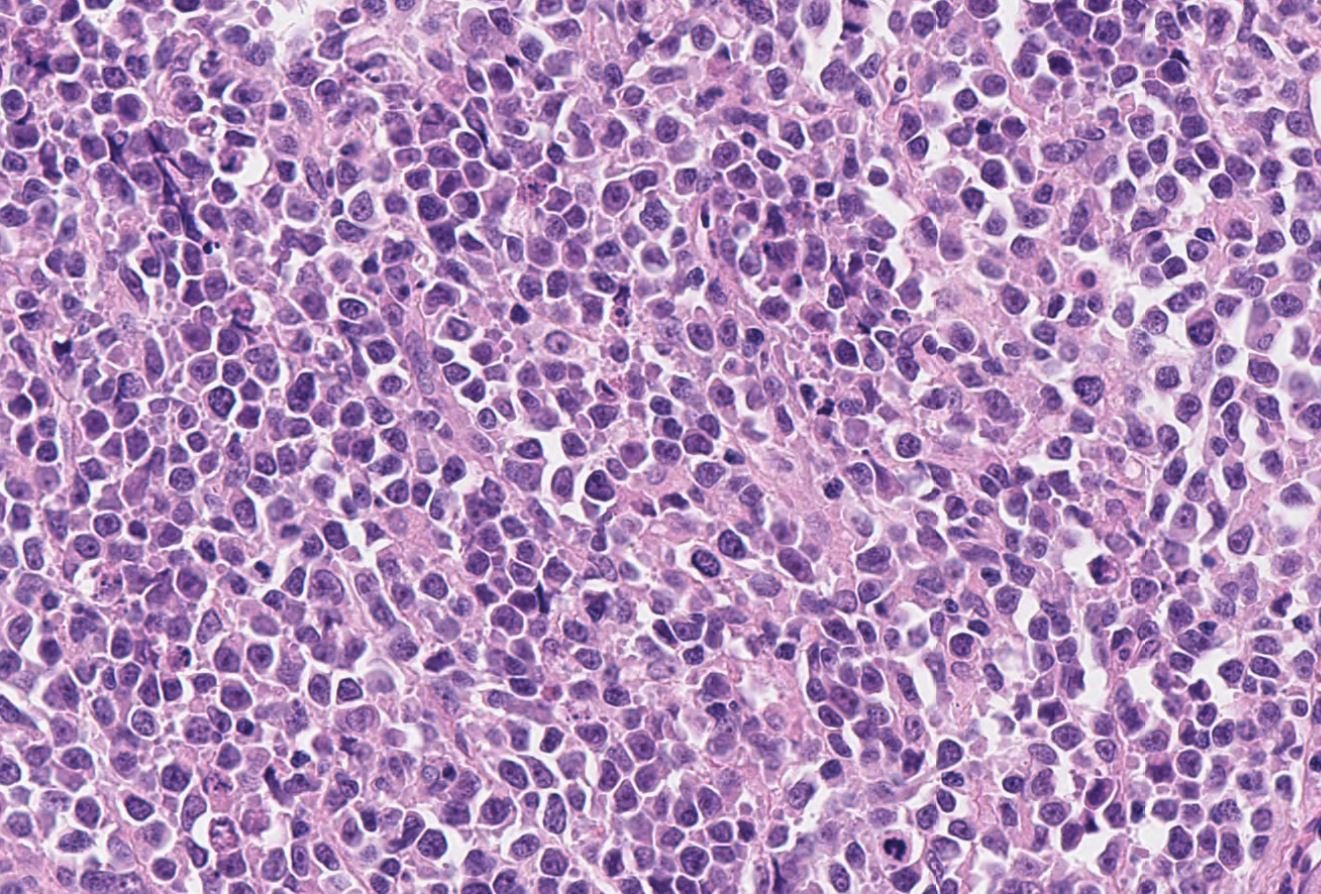

Case: AbdominalWall

Final Diagnosis: